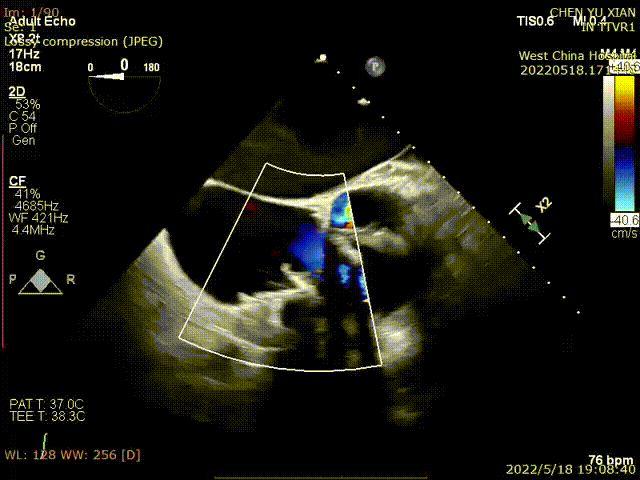

根据术前评估结果,郭应强教授团队为患者量身定制了手术策略,决定使用LuX-Valve Plus经血管三尖瓣置换系统开展手术治疗。手术在全麻下进行,采用经右侧颈静脉入路,在经食道超声和DSA的指引下调整输送器角度以达到正确位置,勾住前瓣后逐步释放盘片,盘片打开后顺利扎针,最终完成瓣膜植入,输送器撤出。术后超声提示人工三尖瓣同轴性良好,瓣架固定牢靠,无反流和瓣周漏,术后三尖瓣平均跨瓣压差为1 mmHg。

术前与术后超声